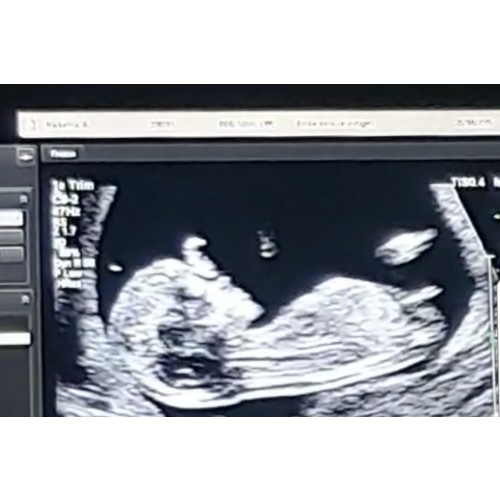

Misschien is deze foto beter 😊

Denk een meisje deze ziet er een beetje tzelfde uit als de mijne en daar gokt ook iedereen meisje op op dit forum ( op facebook zegt weer iedereen jongen maar die van een jongen staat schijnbaar echt duidelijker omhoog )